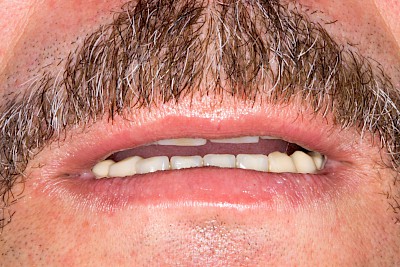

Teilprothese

Teilprothesen sind eine Möglichkeit, Zahnlücken mit einer herausnehmbaren Prothese zu ersetzen.

Eine Sonderform der Teilprothese ist die sogenannte abnehmbare Brücke. Hier kann aufgrund der Zahl und günstigen Verteilung der Restzähne auf rosafarbenen Kunststoff verzichtet werden. Diese Teilprothesen haben einen sehr hohen Tragekomfort und fallen zunächst nicht als herausnehmbarer Zahnersatz auf.

Beispiele mit Klammern 50 Bilder